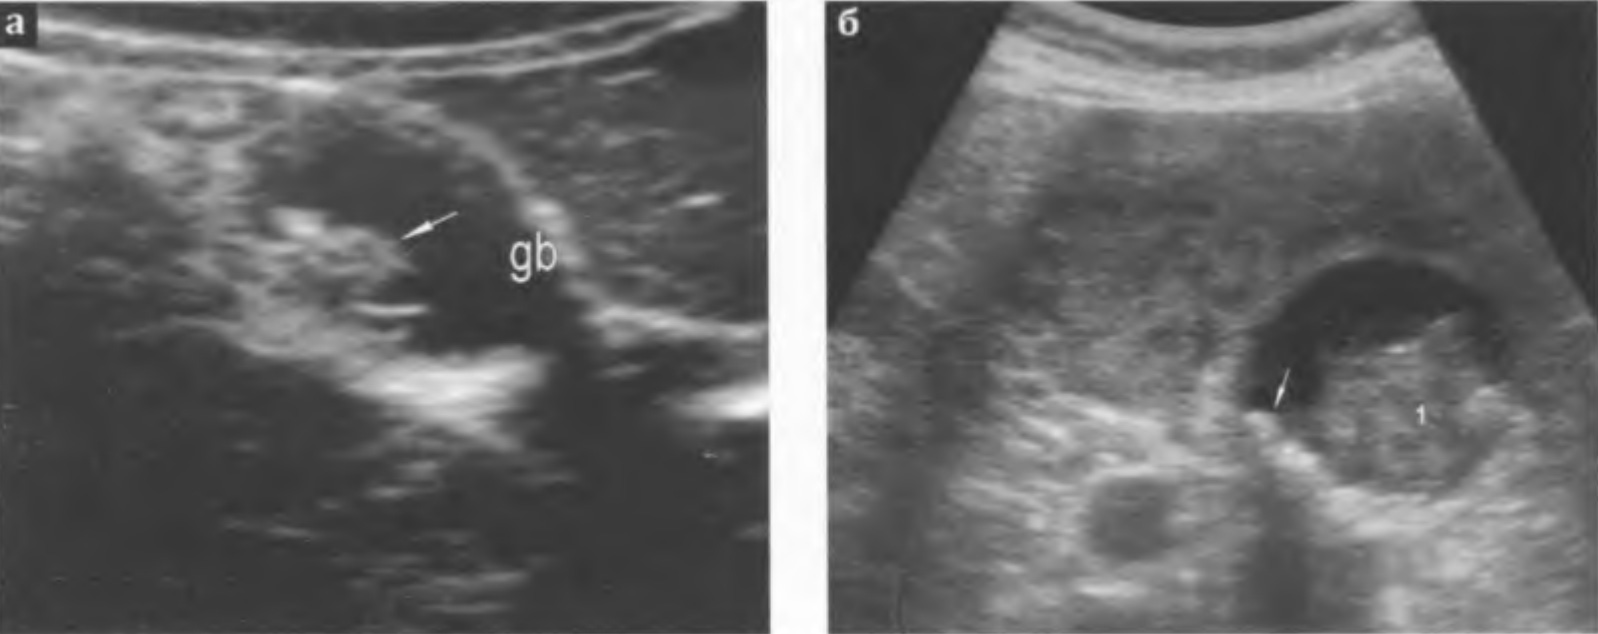

Злокачественные опухоли. Встречаются редко, часто сочетаются с калькулезным холециститом. Ультразвуковая картина во многом зависит от направления роста опухоли (инфильтративный, эндо - или экзофитный, смешанный вариант) и от степени распространенности процесса по стенке пузыря (локальный или диффузный).

Инфильтративная форма. Опухоль прорастает все слои стенки (локально или диффузно), которая значительно утолщена (до 0,8-1,0 см и более), эхогенность ее средняя или пониженная, структура неоднородная, контуры нечеткие. Происходит уменьшение объема полости пузыря.

Эндофитная форма. Опухоль исходит из внутренних слоев стенки. Выявляется в полости желчного пузыря, её размеры более 1,0-1,5 см, эхогенность может быть как средней, так и пониженной. Структура обычно неоднородная, контуры бугристые. Часто внутри опухоли определяются кальцинаты. Стенка пузыря в месте прикрепления опухоли может быть инфильтрирована.

В режиме ЦДК может определяться хаотичный сосудистый рисунок. По мере роста опухолевые массы постепенно занимают весь просвет пузыря, полость перестает определяться. Пузырь приобретает вид гетерогенного образования средней эхогенности, а если в просвете имеются камни, то картина имитирует эмпиему.

Рис. 3.23 а, б. Инфильтративная форма рака желчного пузыря:

а - рак желчного пузыря в сочетании с калькулезным холециститом;

б - желчный пузырь (+...+) плохо дифференцируется от окружающих тканей, просвет его практически не определяется.

Рис. 3.24 а, б. Рак желчного пузыря: а - по задней стенке пузыря (gb), ближе к его дну, выявляется образование средних размеров, средней эхогенности, имеет вид "цветной капусты", умеренно неоднородную внутреннюю структуру (стрелка); отсутствует четкость дифференциации стенки в месте её контакта с образованием;